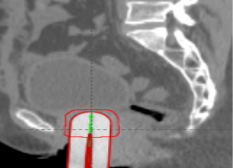

2019年1月8日,湘雅常德医院肿瘤科放射治疗中心成功实施常德市首例三维近距离后装治疗,这给常德及湘西北地区的宫颈癌患者带来了一丝曙光。家住常德武陵区的杨大...